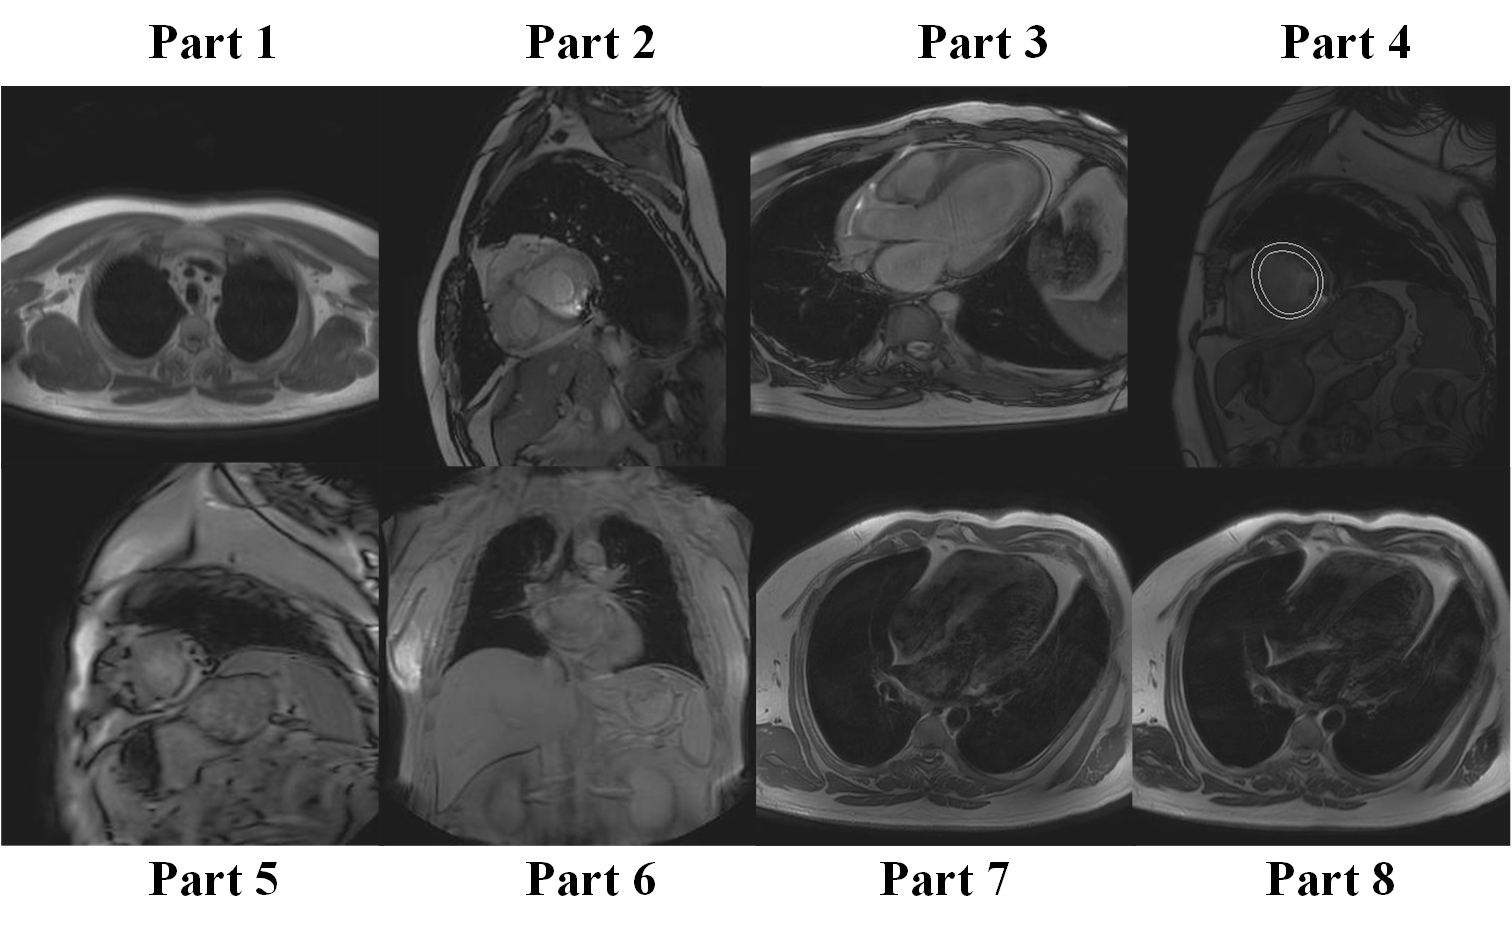

IV-A Training Data

we collect 60 persons’ CMR data from Department of MRI, Fuwai Hospital, Chinese Academy of Medical Science & Peking Union Medical College. There are 30 patients with normal cardiac function and 30 patients with arrhythmia, each patient has 80-120 CMR images scanning from the different heart parts, details of this part are shown in Fig. 7. Totally, there are 5320 images w/o motion artifact which is used for training and 3469 images with motion artifact which are used for testing.

The raw CMR provided by FUWAI Hospital are stored in DICOM format. We transfer each DICOM to the one-channel gray image. Each image was augmented with random rigid transformation which contains random rotation, translate and zoom, then the image was cropped to 256x256 and normalized to . The take 256x256 size images as input.